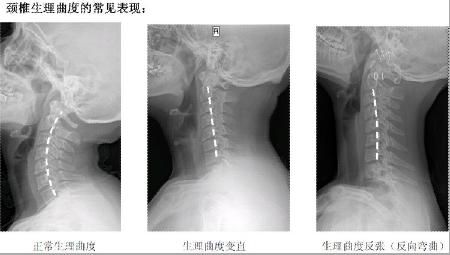

人體的脊椎結(jié)構(gòu)

人體的頸椎結(jié)構(gòu)

正常的人體脊椎生理彎曲圖

頸椎的病變過程

正常頸椎生理彎曲,可以使人呼吸通暢

從上面一組圖我們可以看出,頸椎正常的生理彎曲很重要。但現(xiàn)在,由于電腦的使用,很多人的頸椎都出現(xiàn)了不應(yīng)有的病變,頸曲度消失,甚至反張,會(huì)導(dǎo)致腦血出現(xiàn)障礙,引起包括頭暈、肩頸痛、手臂麻,以及頸心綜合癥等一系列問題,而昆叔正是由客戶的頸紋判定她的頸椎不好的。